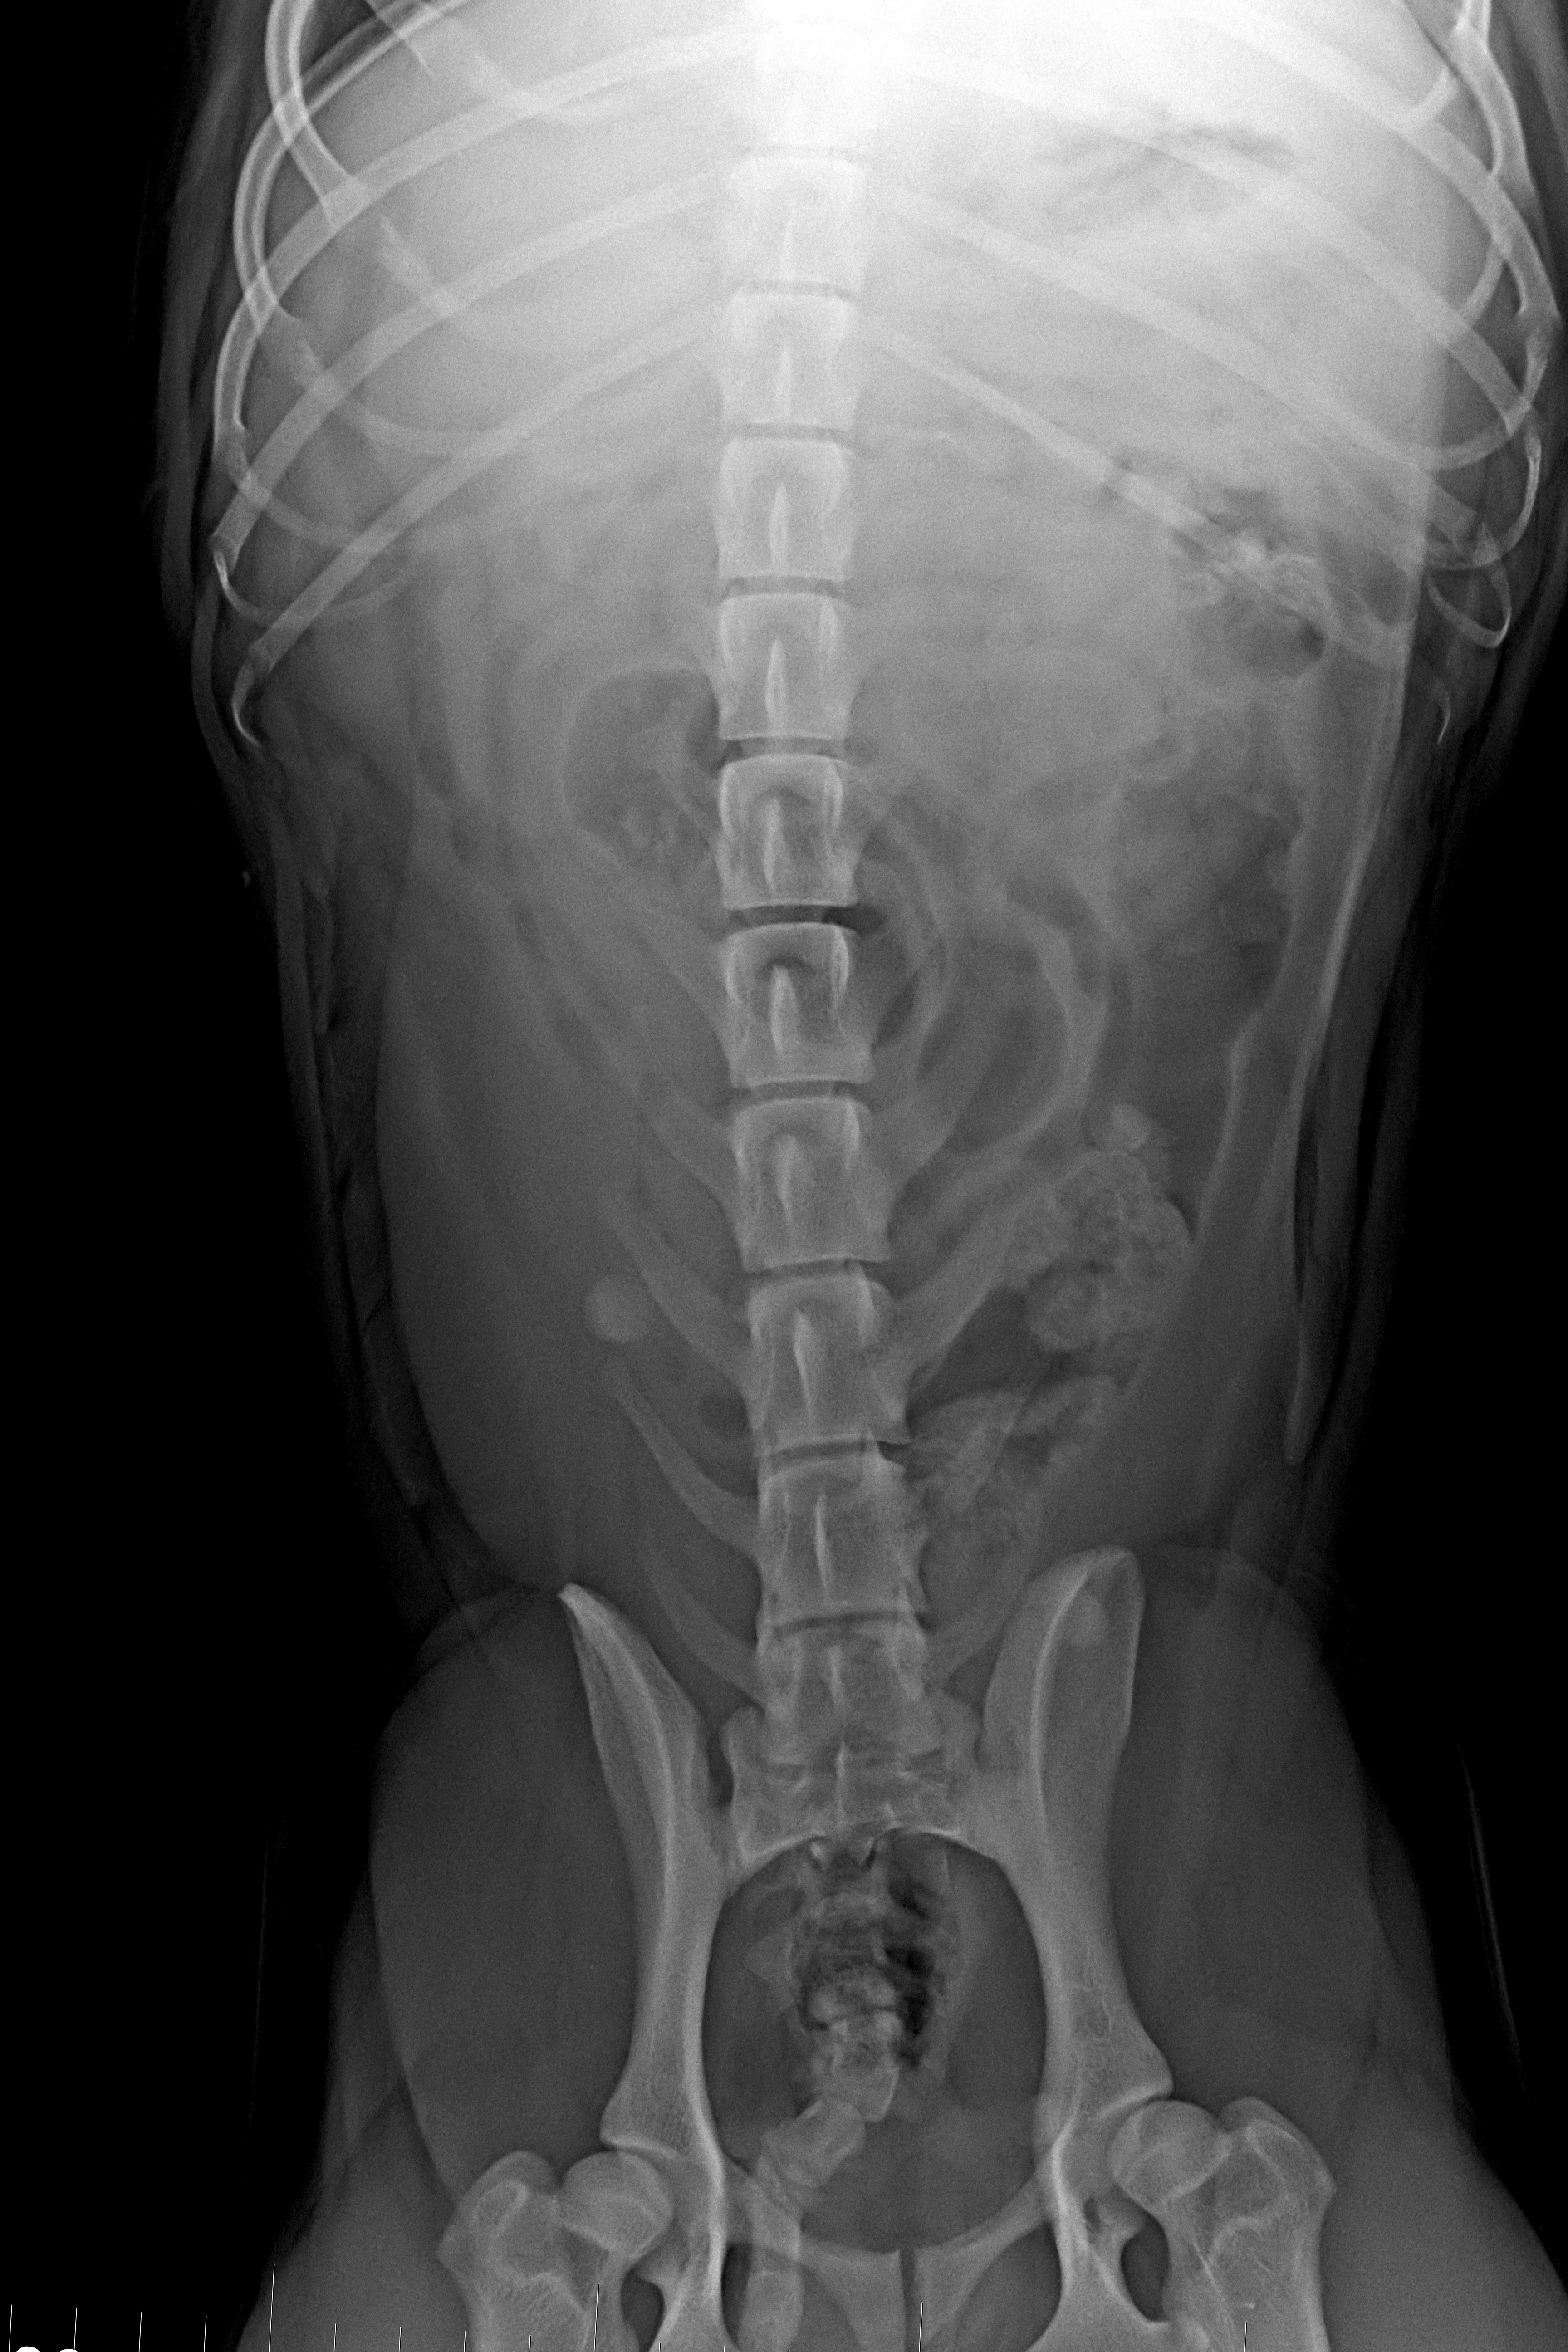

(1) 7 týdnů VD

(1) typ 3

(3) 7 měsíců VD 1

(3) typ 3 po korekci polohy pánve